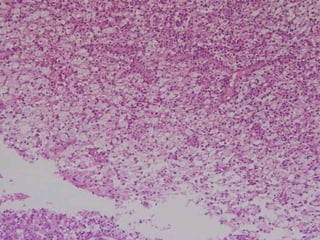

Acute Abscess

 Histopathological

Features:

Zone of liquefaction composed of:

• Exudates.

• Necrotic tissue.

• Dead neutrophils.

Dilated blood vessels.

 Inflammatory [granular cell]

infiltration.